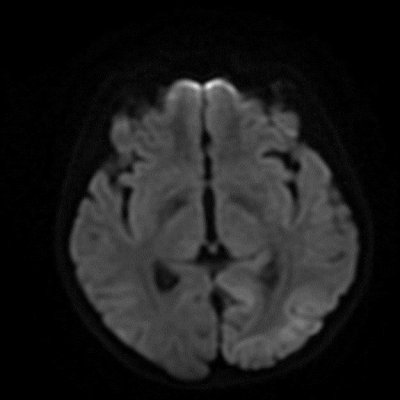

- A) Aksiyel FLAIR görüntülerde parietooksipital lobda kortikal hiperintensite (ok) ve difüzyon görüntülerde kısıtlanma alanları izleniyor (oklar). Ertesi gün çekilen kontrol MRG’de FLAIR serilerde yeni gelişen oksipital bölgede kortikal hiperintensite (ok) izlenmektedir.

- MELAS sendromunun radyolojik özellikleri, klasik iskemik inmeden farklı olarak vasküler sulama alanlarına uymayan ve migratuar stroke-benzeri lezyonlar ile karakterizedir.

- MRG’de akut fazda T2/FLAIR hiperintensiteyle birlikte giral şişme ile karakterize enfarkt-benzeri lezyonlar ve subkortikal beyaz cevher tutulumu görülür. DWI’da artmış sinyal dikkat çekmekle birlikte ADC değerlerinin normal ya da hafif artmış olması, baskın sürecin vazojenik ödem olduğunu gösterir.